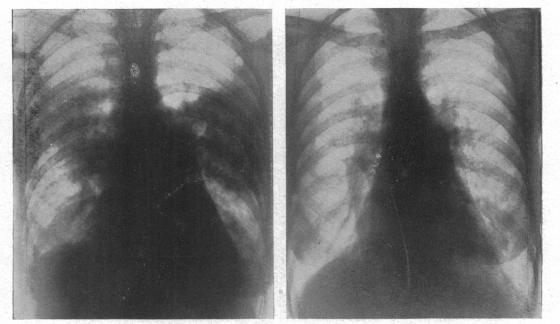

The radiology of acute pulmonary oedema.

Br Heart J. 1951 Oct;13(4):503-18. doi: 10.1136/hrt.13.4.503.